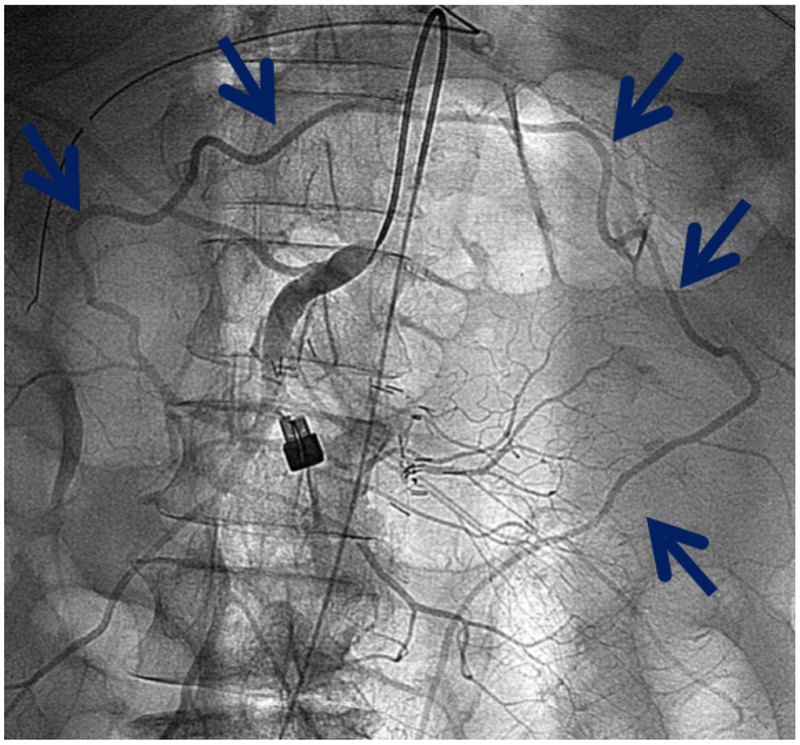

Хроническая окклюзия артерий: причины, симптомы и лечение